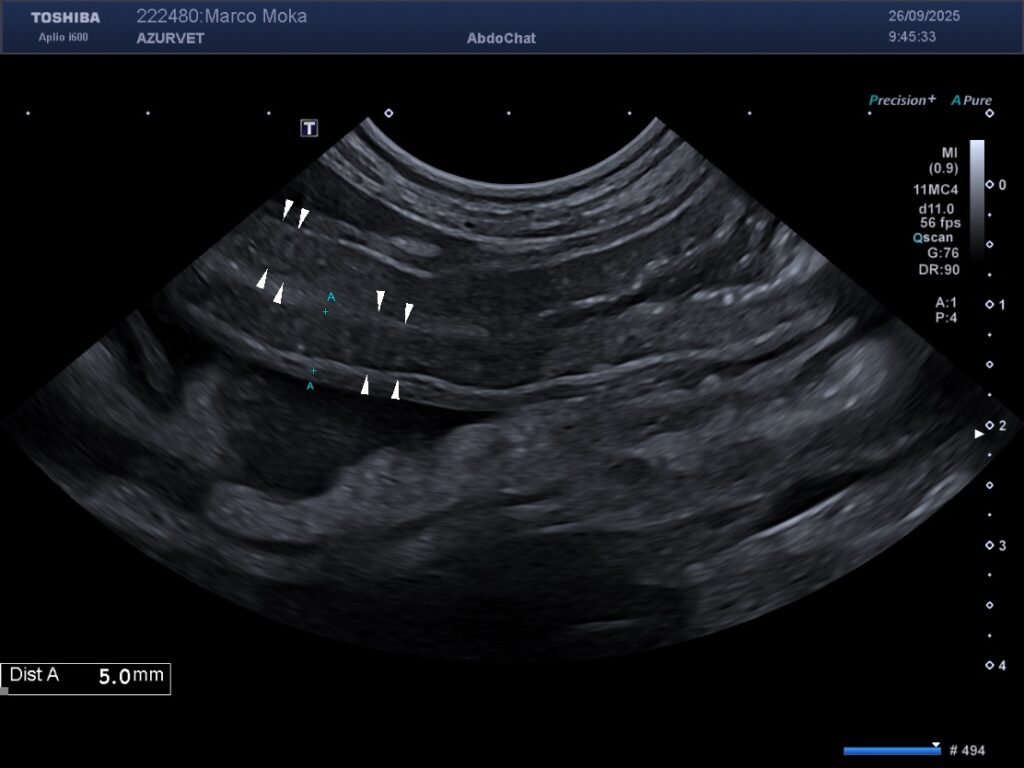

1) Un épaississement de la paroi de la vésicule biliaire lié à un oedème pariétal (secondaire à l’hypoalbuminémie) : figure 2 ci-dessous.

Figure 2 : épaississement pariétal discret de la paroi de la VB chez le même animal que la figure 1.